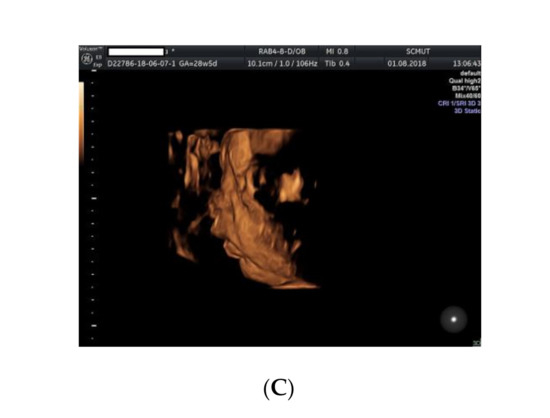

2. Case Presentation